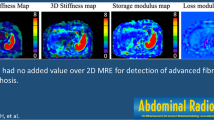

Figure 2 shows MRE, DWI (b = 0 s/mm2) images and ADC, Dt, Dp, as well as f maps for a patient with fibrosis stage 3 and inflammatory activity grade 2.